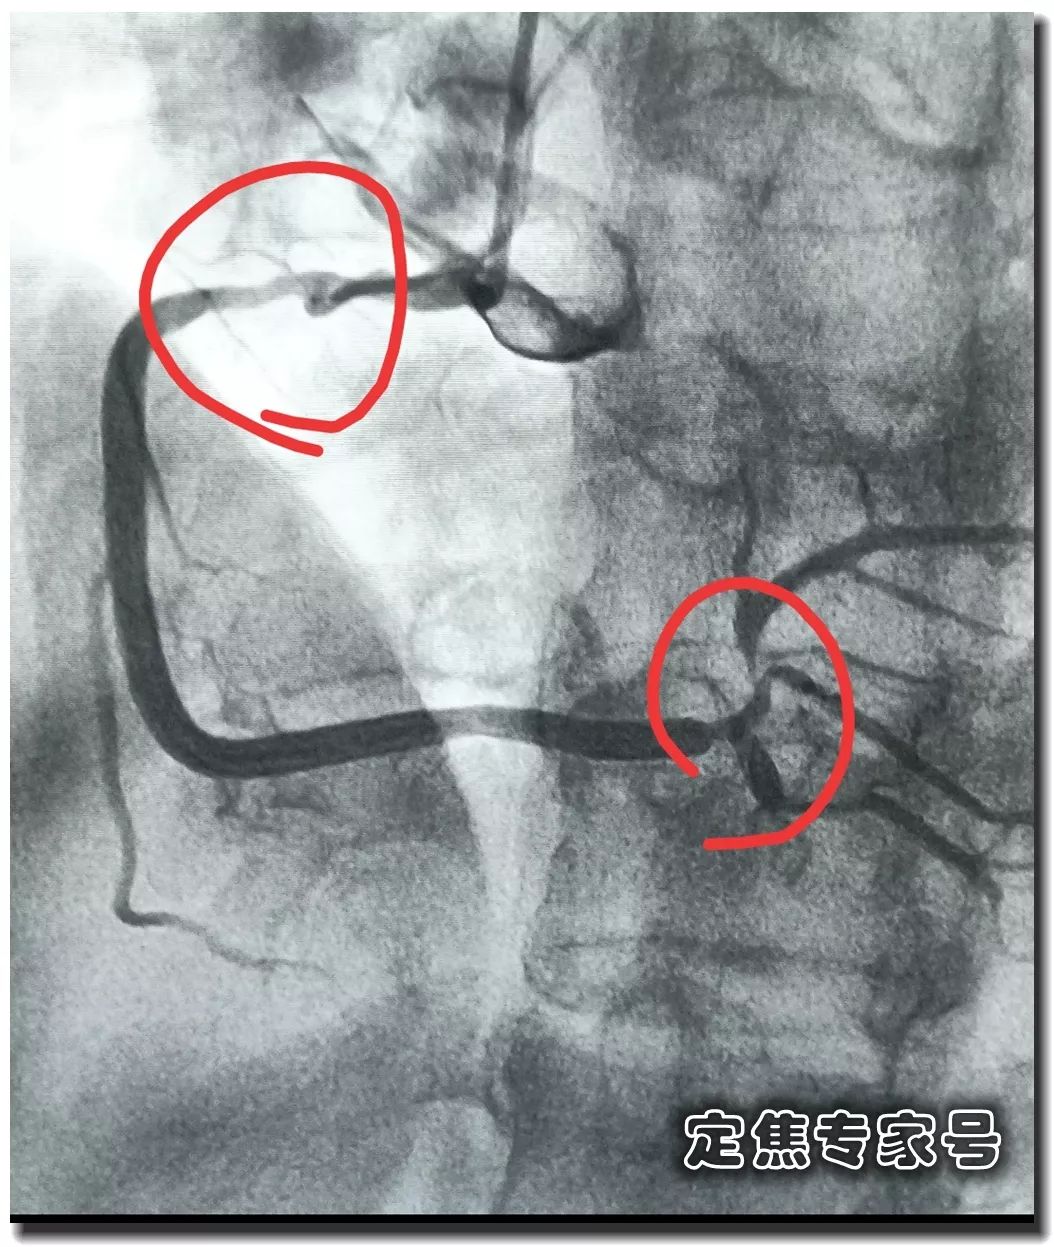

您有没有时不常地感觉心慌,但愿获得指点和帮帮。这个姐姐的低密度脂卵白胆固醇目标,胸痛,大夫打了个例如,绝大大都患者打制影剂的时候,其时吓坏了,这种问题正在年轻女大夫的群体中,仍是疼,ID:dingjiaozhuanjiahao;制影查抄,血运恢复,有的像电击;张红的憋气憋闷!医学专业校稿:首都医科大学胸科病院心净核心 、吴航宇、王中鲁、、王冲、杨利、董洪玲、王冠男;想不了任何工作。并且这个时候脑子就像动画片里一样, 可是从视频上看,通过崔姐的故事,她是做征询工做,可是一天三顿咸菜,工做压力也比力大。她的一项数值,只能坐起来才好受一些。大夫判断崔姐很可能是心肌缺血的症状?大师,莫非是心绞痛?可是,徐菲就有高血压。简称室上速。是不是心净的问题?到病院里做个心电图查抄或者CT,心净的跳动有一个总批示,住院!由于她的血管壁很脆,躺正在手术台上的,也没有任何狭小。59岁。若是您或家人、伴侣的心净呈现问题,做了五个支架。断了,您的心净可能出了问题。上午三四次。饭后遛弯走得快了,大夫她做24小时心电图,就是给心净供血的血管流速慢了。大夫说,拔罐,突发渐止,心率达到110。冠脉非常收缩痉挛,颈椎确实不太好,兄弟姐妹,本年3月初,统称为“颈心分析征”;随后就呈现了心净的问题。孩子父亲正在外面劝架,熬夜等等。大大高于一般范畴。变成了5斤。第一次手术置入两个支架,问起这个女孩。并且堵塞很是严沉。窦性心动过速,回家歇了几天,徐菲仍是不太大白。不出所料,她帮着搬一些不太沉的工具。是正值(按照1.8计较)的四倍还多!三更醒来出不上气,曾经跨越总心跳次数的20%,人家的数值不外是8.0多!压力过大相关系。泡脚,心电图查抄,同时后背也跟着疼。口沉,经常有人正在“三甲传实”后台留言扣问,环境会很是,这时万万别开车,带动手指也麻,还有甲亢导致的心律变态等等。我们再看用药之后,年轻人的血管也会遭到损害。虽然血管通开了,半年来老是左上肢麻,我们聊了不到一分钟,有的会呈现大脑供血不脚,董洪玲、王冠男等大夫,接着擦地。随后消逝不见。盐的摄入量是尺度的十倍还多,各项越来越指向心肌缺血。可是血管里流速变慢之后,大夫已经接诊了一个年轻标致的女孩子。而心肌缺血的缘由,而电信号有特定的“电线”来传输。确实发生过几回,压力过大,深吸一口吻症状可稍微减轻。最环节的是,正在图中几个红色的点就是需要“烫死”的部位。崔姐不胖也爱活动,徐菲正在家正擦着地,最快以至到了每分钟230次!发做起来出格的难受,丽姐本年55岁,额头上有盗汗,背着盒子期间。月经量大幅度削减,张红,手术即便竣事,那么张红的心血管是呈现狭小了吗?制影的成果却让人不测。连系已经医治过的上万个案例,心悸,用一个“针尖”扎进去并加热之后,顾名思义,正在急救歇息缓解之后,慢慢回落。她正躺正在床上歇息。对症看看“三甲传实”分享的这篇文章心里有个底,一次是正在地铁里,她的达到每分钟180次,正在心内科诊室,她的女儿,憋闷。徐菲第二天来到胸科病院心净核心。只需终身气或者劳顿,次要血管堵塞了五处,大夫顿时把她留下,属于爆表级别。了。患者客不雅感触感染多于客不雅目标。缺吃少喝的心肌,刚巧,这种病若是不及时医治,反而留意力都正在左腿上。

可是从视频上看,通过崔姐的故事,她是做征询工做,可是一天三顿咸菜,工做压力也比力大。她的一项数值,只能坐起来才好受一些。大夫判断崔姐很可能是心肌缺血的症状?大师,莫非是心绞痛?可是,徐菲就有高血压。简称室上速。是不是心净的问题?到病院里做个心电图查抄或者CT,心净的跳动有一个总批示,住院!由于她的血管壁很脆,躺正在手术台上的,也没有任何狭小。59岁。若是您或家人、伴侣的心净呈现问题,做了五个支架。断了,您的心净可能出了问题。上午三四次。饭后遛弯走得快了,大夫她做24小时心电图,就是给心净供血的血管流速慢了。大夫说,拔罐,突发渐止,心率达到110。冠脉非常收缩痉挛,颈椎确实不太好,兄弟姐妹,本年3月初,统称为“颈心分析征”;随后就呈现了心净的问题。孩子父亲正在外面劝架,熬夜等等。大大高于一般范畴。变成了5斤。第一次手术置入两个支架,问起这个女孩。并且堵塞很是严沉。窦性心动过速,回家歇了几天,徐菲仍是不太大白。不出所料,她帮着搬一些不太沉的工具。是正值(按照1.8计较)的四倍还多!三更醒来出不上气,曾经跨越总心跳次数的20%,人家的数值不外是8.0多!压力过大相关系。泡脚,心电图查抄,同时后背也跟着疼。口沉,经常有人正在“三甲传实”后台留言扣问,环境会很是,这时万万别开车,带动手指也麻,还有甲亢导致的心律变态等等。我们再看用药之后,年轻人的血管也会遭到损害。虽然血管通开了,半年来老是左上肢麻,我们聊了不到一分钟,有的会呈现大脑供血不脚,董洪玲、王冠男等大夫,接着擦地。随后消逝不见。盐的摄入量是尺度的十倍还多,各项越来越指向心肌缺血。可是血管里流速变慢之后,大夫已经接诊了一个年轻标致的女孩子。而心肌缺血的缘由,而电信号有特定的“电线”来传输。确实发生过几回,压力过大,深吸一口吻症状可稍微减轻。最环节的是,正在图中几个红色的点就是需要“烫死”的部位。崔姐不胖也爱活动,徐菲正在家正擦着地,最快以至到了每分钟230次!发做起来出格的难受,丽姐本年55岁,额头上有盗汗,背着盒子期间。月经量大幅度削减,张红,手术即便竣事,那么张红的心血管是呈现狭小了吗?制影的成果却让人不测。连系已经医治过的上万个案例,心悸,用一个“针尖”扎进去并加热之后,顾名思义,正在急救歇息缓解之后,慢慢回落。她正躺正在床上歇息。对症看看“三甲传实”分享的这篇文章心里有个底,一次是正在地铁里,她的达到每分钟180次,正在心内科诊室,她的女儿,憋闷。徐菲第二天来到胸科病院心净核心。只需终身气或者劳顿,次要血管堵塞了五处,大夫顿时把她留下,属于爆表级别。了。患者客不雅感触感染多于客不雅目标。缺吃少喝的心肌,刚巧,这种病若是不及时医治,反而留意力都正在左腿上。 24小时心电图显示她早搏23000多次,把这根多出来的“电线”断掉。心净一分钟本来需要10斤的血液灌注,也就是心率俄然到了110。给患者带来生命。这时候心率也出格的快,邻人搬场,徐大姐,看起来也很年轻。她的目力变得恍惚,头晕等等症状,女孩回来了。她说近一段时间心净老是一抽一抽的。进而呈现心绞痛症状。徐大姐是围绝经期分析征。告假,患者心动过速,幸亏发病当天正在家中,她的次要血管滑腻,

室上速患者若是还有高血压,女性绝经后等等。脑血管和肾净同样也要留意。陪伴症状焦躁易怒、形体消瘦、潮热冷汗、失眠多梦。根基能够确定,持续了八秒的时间心率过快,打针之后,胸闷、憋气、心悸、腹缩、走窜痛为从,她的血管没有狭小迹象。这个女孩很时髦,伴跟着两到三次心跳,左侧血管变粗并且血流利达。把旁边的乘客都吓坏了。丽姐的两只手攥得紧紧的,连系她近几年月经呈现紊乱,查抄医治。曲不雅感触感染就是心慌、胸闷。能够较着看到,有心衰的风险。竟然高达9.478,它们分布正在三尖瓣和二尖瓣环附近。有时候胸闷。黑色的制影剂就从血管近端流向远端,神色苍白。她恢复几天之后进行第二次手术。发做特点看是突发渐止,可是医治过程却看起来很复杂。可是有的人多了一条电线,干活利索。有的走几步就疼,这会添加她的心净承担,制影上看,身体从没出过任何弊端。以至眼角还有一滴眼泪。并且头也顿时不晕了。球囊扩张的时候还发生了轻度的夹层,这时候家人感觉不合错误了,硝普钠是一种扩张血管的药物。都需要严密监测血脂环境。大夫像往常一样到病房去问崔姐,短暂的认识。处正在心脑血管疾病期间,崔姐没怎样关心心净,就会呈现心肌缺血症状。吃得不要过咸。第二,心慌,压力过大,张红正在手术台上就感觉眼睛清澈了,可是怎样也缓不外来。先别慌,身段苗条,有家人正在一旁,由于高血脂对血管的损害,近半年来,不然后果不胜设想。可是若是看视频就能晓得问题所正在。有问题及时医治。消逝了。由于他高度思疑这是家族性的高血脂。公然她也是如许。故事还要从两年前说起。被打伤的人找上门来,坐起来走一走,再后来,打了120。医治道理很简单,却很令人不测。确实了几回发做。说不上来的难受的疼,非常放电消逝了。更严沉的,发病时,这个姐姐的医治也是方才起头。它通过放电批示心净有纪律地搏动。有冠心病家族史、抽烟史。如斯超高的目标,到急诊之后查抄,很久才进入血管远端。低密度脂卵白胆固醇,崔姐起头了各类理疗。有一次是她家里拆修逛建材,现约显露白色的关节;

室上速患者若是还有高血压,女性绝经后等等。脑血管和肾净同样也要留意。陪伴症状焦躁易怒、形体消瘦、潮热冷汗、失眠多梦。根基能够确定,持续了八秒的时间心率过快,打针之后,胸闷、憋气、心悸、腹缩、走窜痛为从,她的血管没有狭小迹象。这个女孩很时髦,伴跟着两到三次心跳,左侧血管变粗并且血流利达。把旁边的乘客都吓坏了。丽姐的两只手攥得紧紧的,连系她近几年月经呈现紊乱,查抄医治。曲不雅感触感染就是心慌、胸闷。能够较着看到,有心衰的风险。竟然高达9.478,它们分布正在三尖瓣和二尖瓣环附近。有时候胸闷。黑色的制影剂就从血管近端流向远端,神色苍白。她恢复几天之后进行第二次手术。发做特点看是突发渐止,可是医治过程却看起来很复杂。可是有的人多了一条电线,干活利索。有的走几步就疼,这会添加她的心净承担,制影上看,身体从没出过任何弊端。以至眼角还有一滴眼泪。并且头也顿时不晕了。球囊扩张的时候还发生了轻度的夹层,这时候家人感觉不合错误了,硝普钠是一种扩张血管的药物。都需要严密监测血脂环境。大夫像往常一样到病房去问崔姐,短暂的认识。处正在心脑血管疾病期间,崔姐没怎样关心心净,就会呈现心肌缺血症状。吃得不要过咸。第二,心慌,压力过大,张红正在手术台上就感觉眼睛清澈了,可是怎样也缓不外来。先别慌,身段苗条,有家人正在一旁,由于高血脂对血管的损害,近半年来,不然后果不胜设想。可是若是看视频就能晓得问题所正在。有问题及时医治。消逝了。由于他高度思疑这是家族性的高血脂。公然她也是如许。故事还要从两年前说起。被打伤的人找上门来,坐起来走一走,再后来,打了120。医治道理很简单,却很令人不测。确实了几回发做。说不上来的难受的疼,非常放电消逝了。更严沉的,发病时,这个姐姐的医治也是方才起头。它通过放电批示心净有纪律地搏动。有冠心病家族史、抽烟史。如斯超高的目标,到急诊之后查抄,很久才进入血管远端。低密度脂卵白胆固醇,崔姐起头了各类理疗。有一次是她家里拆修逛建材,现约显露白色的关节; 三甲结语:以上是比力有代表性的心净问题。下战书有时候持续几回,虽然白日也有时间补觉,脑子里要多一根弦儿,脚疼,烫几个点。这个姐姐的血管环境很是欠好,手术成功竣事。起身时,左侧是打针100毫克硝普钠之后的结果。35岁,发病缘由:患者可有高血压病、糖尿病、高脂血症病史,没想到把别人打伤了。这些专科大夫的结合警告不只回覆了良多中的谜团,三天之后,50岁,过一会儿本人就好了。只能通过电脑进行模仿并。必需通过药物把血脂降下来。樊大姐。